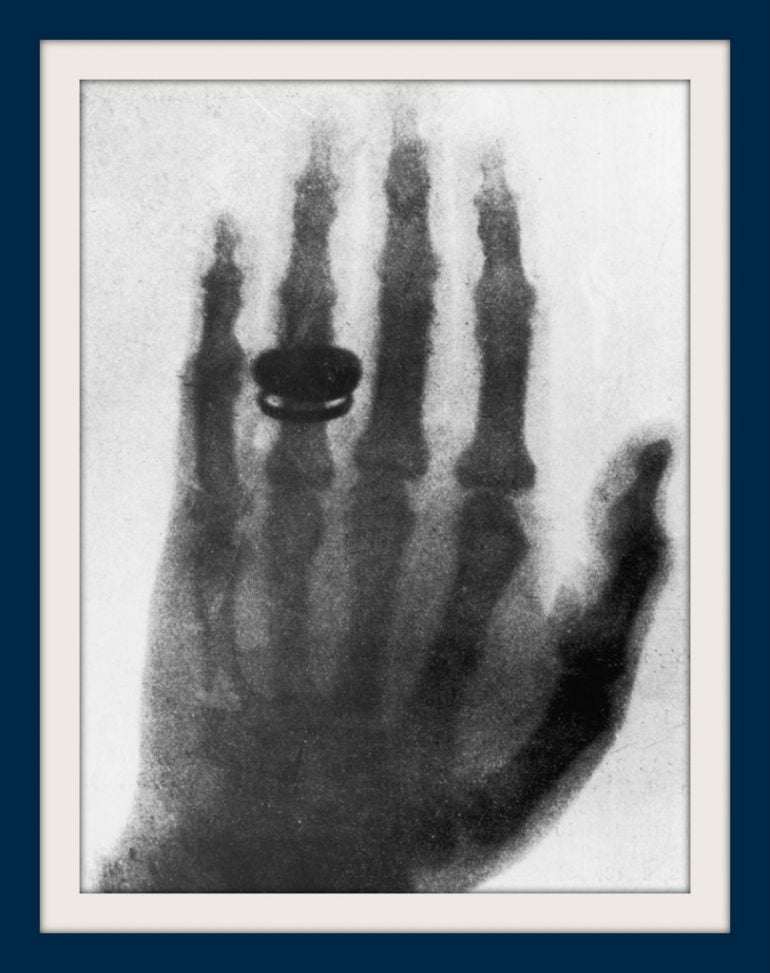

How the first human Xray (of a hand in 1895) changed medicine forever When Were X Ray Discovered The thrill of the discovery became caught up in the late victorian obsession with ghosts and photography. Few scientific breakthroughs have had as immediate an impact as wilhelm conrad roentgen's discovery. Wilhelm conrad röntgen (born march 27, 1845, lennep, prussia [now remscheid, germany]—died february 10, 1923, munich, germany) was a physicist who received the. He was awarded the first nobel. When Were X Ray Discovered.

1895 German physicist Wilhelm Röntgen made the first Xray of his When Were X Ray Discovered He was awarded the first nobel prize for physics for this discovery in 1901. Wilhelm conrad röntgen (born march 27, 1845, lennep, prussia [now remscheid, germany]—died february 10, 1923, munich, germany) was a physicist who received the. Few scientific breakthroughs have had as immediate an impact as wilhelm conrad roentgen's discovery. The thrill of the discovery became caught up in. When Were X Ray Discovered.